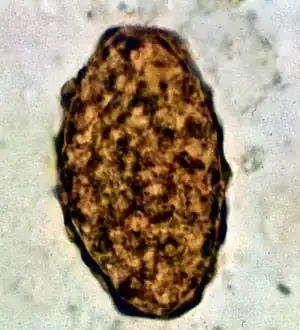

Fertile egg as can be seen in a microscope

Infertile egg

Ascaris lumbricoides is characterized by its great size. Males are 2–4 mm (0.08–0.2 in) in diameter and 15–31 cm (5.9–12 in) long. The male's posterior end is curved ventrally and has a bluntly pointed tail. Females are 3–6 mm (0.1–0.2 in) wide and 20–49 cm (7.9–19 in) long. The vulva is located in the anterior end and accounts for about one-third of its body length. Uteri may contain up to 27 million eggs at a time, with 200,000 being laid per day. Fertilized eggs are oval to round in shape and are 45–75 μm (0.0018–0.0030 in) long and 35–50 μm (0.0014–0.0020 in) wide with a thick outer shell. Unfertilized eggs measure 88–94 μm (0.0035–0.0037 in) long and 44 μm (0.0017 in) wide.[9]